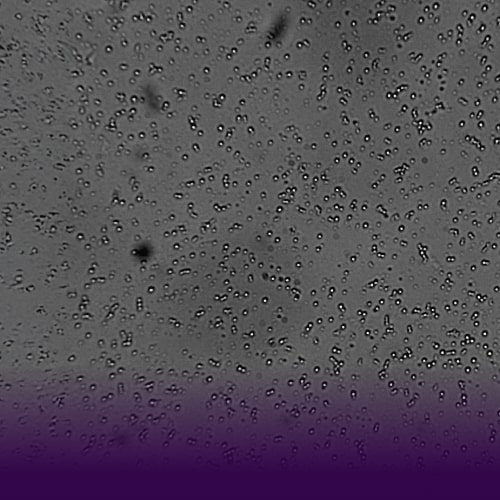

Accurate assessment of globule size supports regulatory compliance by confirming that the formulation meets predefined specifications. Optical microscopy is especially effective for emulsions made from liquids with differing refractive indices, providing direct visualization of globules size and distribution. These metrics are critical indicators of a product’s physical stability.

During the development of topical pharmaceuticals, bright-field microscopy is the most effective technique for visualizing globule size in emulsions. This method is commonly used to evaluate Q1/Q2 excipient combinations and their ability to form a stable microstructure (Q3), which in turn influences physical stability.

The biggest challenge in globules size analysis lies in preparing samples without disrupting the distribution. Bright-field and polarized light microscopy are standard techniques, with the former being particularly well-suited for emulsions. Automated microscopy, paired with statistical imaging tools, ensures reproducibility across batches.

ImageProVision’s patented software enables precise determination of globule size and evaluation of microstructure in both semi-solid and emulsion-based topical products. It offers resolution down to 0.5 µm using optical microscopy, and can be adapted for nano-range analysis using SEM images.